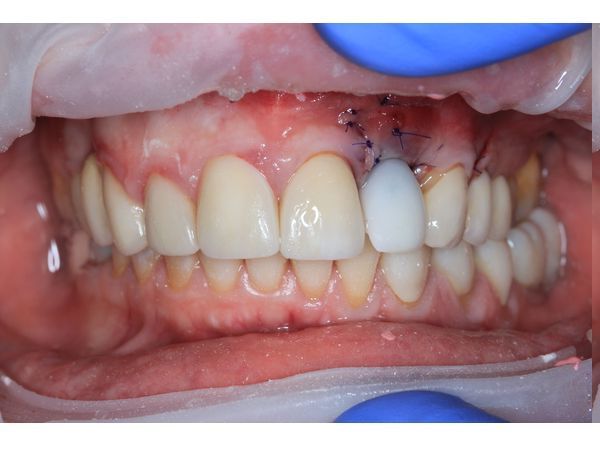

Пациентке сделали анестезию и сформировали микрохирургический доступ для удаления зуба и установки дентального импланта в оптимальную ортопедическую позицию. В зоне дефекта одна треть импланта осталась обнажённой.

Отсутствующую кортикальную пластинку реконструировали с помощью тройного трансплантата из зоны бугра верхней челюсти (забор произвели на стороне вмешательства). Чтобы зафиксировать трансплантат, его утрамбовали в зону дефекта.

Одновременно с этим изготовили временную коронку из пластмассы на титановом основании.